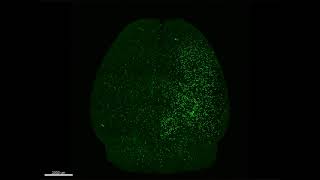

Supplementary Movie Whole Brain Imaging Acut 3D video

Supplementary Movie Whole Brain Imaging Acut 3D

Supplementary Movie Whole Brain Imaging Acut 3D